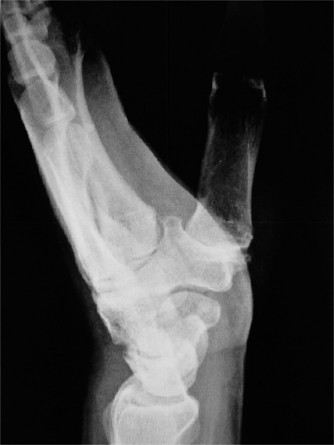

-

ray (Fig. 3–11) taken at the time of the visit is as shown. The radiologist reports this as SLAC wrist. What does SLAC stand for?

Figure 3–11(©) Sunil Thirkannad and Christine M. Kleinert.

The correct answer is (C).

The correct answer is (B). The patient has a severe SLAC wrist with involvement of the midcarpal joint. Loss of cartilage over the proximal pole of the capitate precludes a proximal row carpectomy. By the same token, interposition arthroplasty at the radio carpal joint alone fails to address the midcarpal problem. The use of a silastic prosthesis for the scaphoid has been abandoned due to very high rates of failure. Objectives: Did you learn...? Properly perform the Watson’s test? Identify a SLAC wrist and treat it? CASE 13 ### A patient presents with a history of chronic wrist pain of 6 years duration. He stated that he sustained a fall 9 years ago. Immediately after injury, he did not seek any medical attention, thinking that he had merely sprained his wrist. An xray taken at this visit is shown (Fig. 3–12). What does he have?